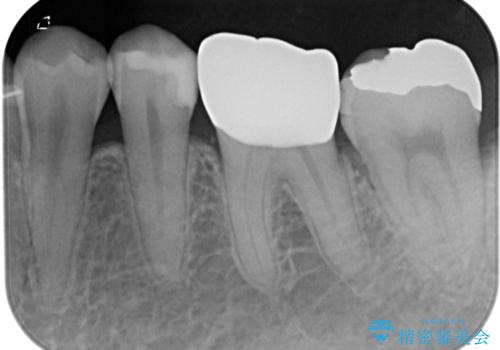

- メタルインレー(保険の金属の詰め物)が取れたとのことで来院された患者様です。

拡大鏡視野下にて、メタルインレーの範囲が大きく虫歯もあったため、オールセラミッククラウンにて修復を行いました。

型どりはシリコーン印象材にて型どりしています。